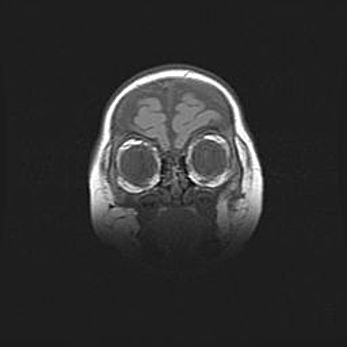

Мальформация Денди-Уокера. Киста задней черепной ямки.

Агенезия мозолистого тела.

Возраст: 2,5 месяца

Вес: 2420 г

Пол: женский

Окружность головы: 37 см

Срок гестации: 32 недели

Мальформация Денди—Уокера — редкий вид патологии ЦНС, представляющий собой врожденный порок развития каудального отдела ствола и червя мозжечка, ведущий к неполному раскрытию срединной (Мажанди) и латеральных (Лушка) апертур IV желудочка мозга. Для этогно синдрома характерна триада симптомов: гипотрофия червя мозжечка и/или полушарий мозжечка, кисты задней черепной ямки, гидроцефалия различной степени. В 70% случаев порок сочетается и с другими аномалиями головного мозга, в частности с агенезией мозолистого тела.